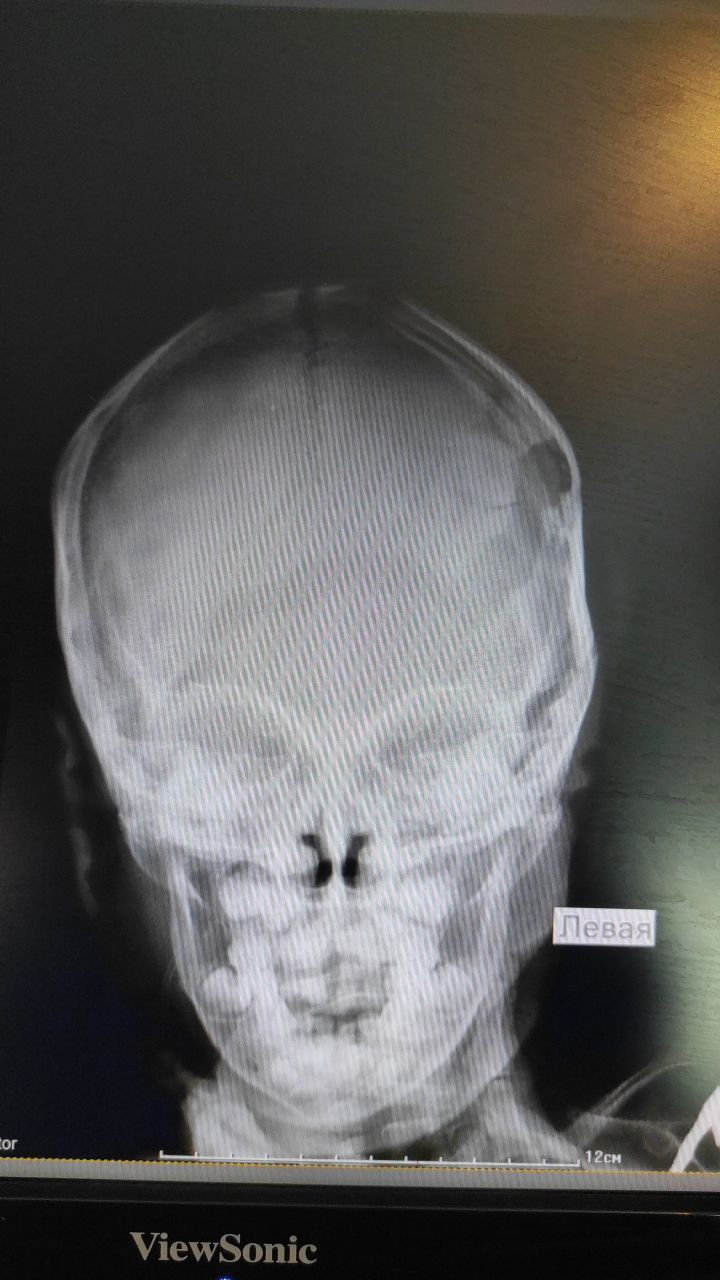

Tohtasin Abdukarimov in Radiology/Рентгенология Чат

Мальчик 3 года

Упал

TA

В бессознание